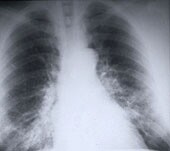

WEDNESDAY, Aug. 7 (HealthDay News) — Certain characteristics of tumors in lung cancer patients are associated with a strong risk of cancer recurrence after surgery, according to a new study.

The study authors examined tumors from more than 700 patients who had surgery for early-stage adenocarcinoma, the most common type of non-small cell lung cancer. Tumors in 40 percent of the patients had an abnormal cell pattern that was strongly associated with cancer recurrence after surgery.

Limited lung surgery may not be appropriate for patients with this micropapillary (MIP) pattern, the Memorial Sloan-Kettering Cancer Center researchers said. They found that patients with the MIP pattern had a 34 percent risk of their lung cancer returning within five years after lung-sparing surgery, or limited resection, in which the tumor is removed by minimally invasive means and lung function is preserved.

In contrast, patients with the MIP pattern who had up to one-third of the lung removed along with the tumor, or lobectomy, had a 12 percent risk of cancer recurrence within five years.